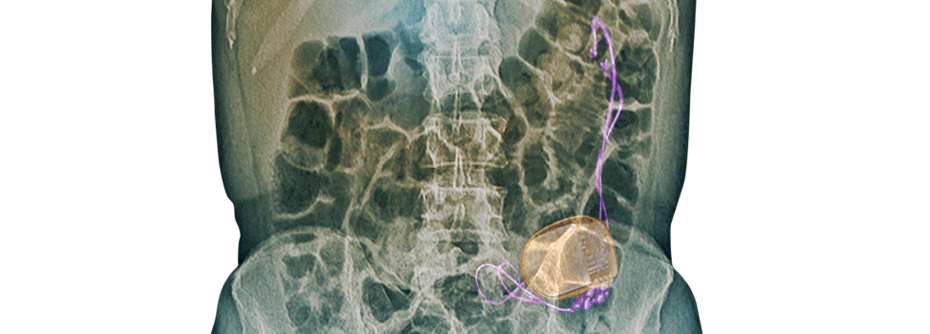

In der CT wird die Ursache meist sichtbar

Koliken und Erbrechen über mehr als 24 Stunden sind immer ein Grund, nach einem Darmverschluss zu suchen. Das klinische Zeichen eines aufgeblähten Bauchs kann bei einem hohen Verschluss fehlen und ist auch bei adipösen Patienten oft schwierig festzustellen. Besonders wichtig: Weder normale Darmgeräusche noch Stuhl im Rektum schließen die Diagnose Darmverschluss aus. Denn die Stille im Darm ist ein relativ spätes Zeichen. Auch Peritonismuszeichen wird man nicht finden, solange keine Darmperforation oder ein Darm­infarkt eingetreten ist. Bildgebendes Verfahren der Wahl ist die abdominale CT. Sie lässt nicht nur frühzeitig die Obstruktion selbst erkennen, sondern in den meisten Fällen auch die Ursache dafür.